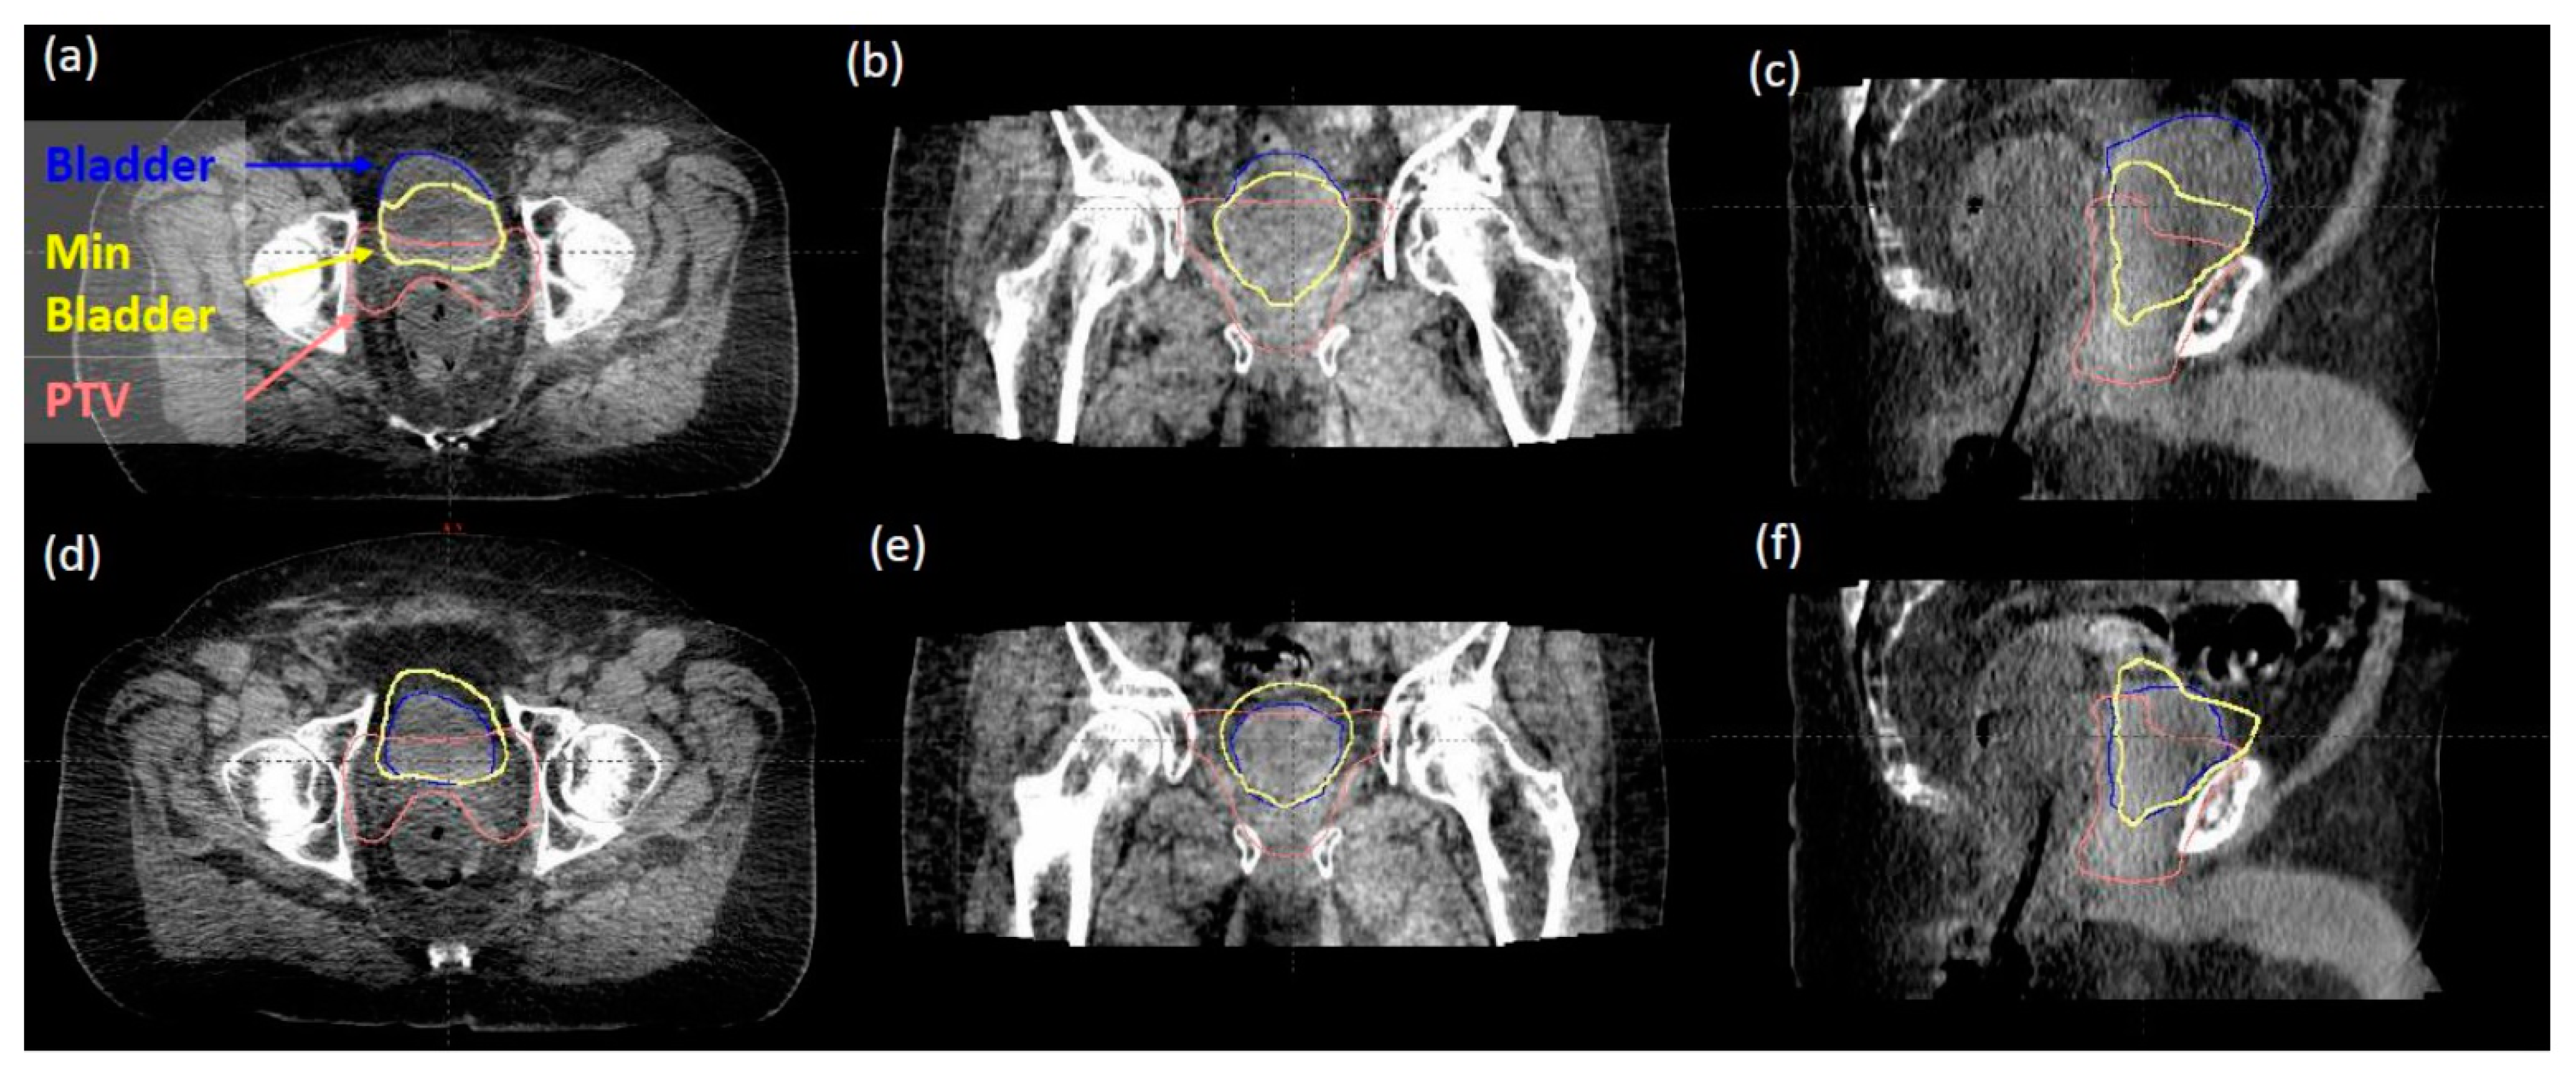

In reviewing 314 daily iCBCT images for 14 patients, the initial mean bladder volume at simulation was 319.325 mL (range 113.63–562.66 mL), while the daily bladder volume ranged from 62.4 mL to 590.7 mL over the course of treatment. There was a 29% to 286% variation observed from daily CBCTs compared to the initial bladder volume at simulation. The maximum dose to the bladder D0.03mL <103–108% with large variations in daily bladder volume is reported in Figure 3a. All cases were below our institutional max bladder dose of 108%, with no differences seen in patients with or without ERB. The bladder dose constraint V65% <60% (with respect to daily bladder volume) was met in 309 of 314 fractions (Figure 3b). A “minimum bladder” contour was created by expanding the PTV in the superior and anterior directions by 15 mm and then intersecting this volume with the planning bladder volume. The value of 15 mm was determined based on the consensus of our genitourinary (GU) expert physicians, as well as an estimate of the photon dose fall-off distance to below 20% of the prescription dose. This “minimum bladder” structure was validated based on what visually separated the daily bladder volumes that failed the V65% <60% constraint from the bladder volumes that passed. Figure 4 demonstrates examples of how the minimal bladder contour differentiates between passing (Figure 4a–c) and failing the V65 <60% constraint (Figure 4d–f). The daily bladder volumes in the five failing fractions all failed to completely extend anteriorly and superiorly beyond this “minimum bladder” contour. Figure 1b further shows that the V65 of the bladder decreases as the daily volume of the bladder increases.

Figure 4.

(a–c) an example of a daily bladder volume that passed the V65% >60% constraint. The bladder (blue) extends anteriorly and superiorly beyond the “minimum bladder” contour (yellow). (d–f) An example of a daily bladder volume that failed the V65% >60% constraint. The bladder does not completely extend anteriorly and superiorly beyond the “minimum bladder” contour.